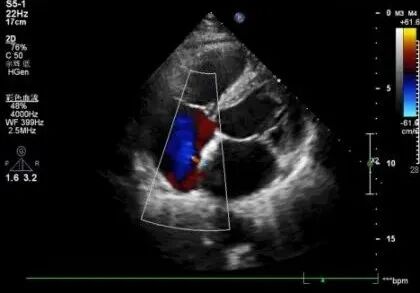

这不仅困扰着患者与家属,也成为摆在医生面前的难题。常规经胸心超提示,患者心脏房间隔可能存在一个极细微的“卵圆孔未闭”。然而图像朦胧,难以定论。这是一个隐蔽的“心眼”,却可能是血栓潜入大脑的通道。若不能证实,患者将面临复发风险;若不能精准评估,治疗便无从谈起。

右心声学造影

诊断的明确,为患者打开了根治的希望之门。沈先生后续进行了卵圆孔未闭封堵术,从此摆脱了脑中风的复发阴影。